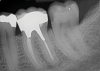

The material used to fabricate a post should be considered as well. Both cast and prefabricated options are available, but there is no consensus regarding the effect of cast versus prefabricated posts on survival rates, and different studies have found opposing results.5,16 The most common materials used in posts are metal and fiber. Both materials have been associated with similar survival rates.17 In teeth with no remaining coronal walls or an absence of ferrule, posts with higher values of elastic modulus, such as fiber posts, have been shown to result in better clinical outcomes when compared with metal posts.18 However, in teeth with at least one remaining coronal wall, restorations with fiber and metal posts demonstrated similar survival rates.18 The choice of which material to use should be based on the specific case and patient factors (Figure 4 and Figure 5).

(4.) Radiographs of teeth treated with prefabricated and custom cast posts, respectively.

Figure 4